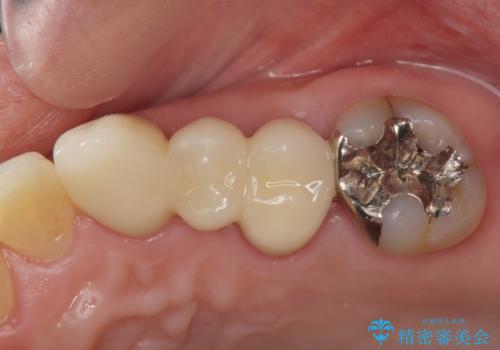

インプラント治療を行うには隙間が狭すぎるためブリッジか入れ歯をご提案したところ、取り外しの必要な入れ歯は希望されずブリッジを用いて機能・審美性の改善を行っていくこととなりました。

ブリッジの長期的な予後のためには支台となる歯の位置・清掃性が重要となりますが、今回ブリッジを製作するにあたり位置の悪い左上小臼歯を補綴前小矯正を行い位置を改善します。

矯正を行うことで歯を適切な位置に動かすことでより、清掃性に優れ長期的な予後を見込むことのできるブリッジを製作することができました。